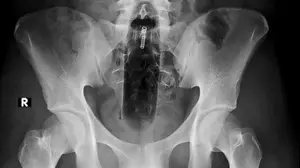

ככה זה נראה בגוף: התופעה הבריאותית שהשתלטה על ישראל אחרי 7.10